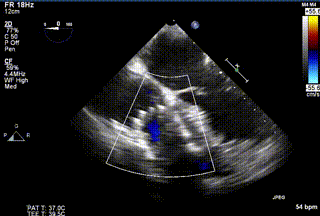

三例患者入院后,葛均波院士團隊周達新教授、潘文志教授、張源博士、陳莎莎博士及心超室的潘翠珍教授、李偉教授對患者的情況進行詳細評估和討論,最終決定為三例患者選擇LuX-Valve Plus40mm、50mm和50mm型號的瓣膜進行手術治療。手術后即刻拔除氣管插管,術后患者三尖瓣反流癥狀得到顯著改善,復查心超結果顯示人工三尖瓣瓣膜支架固定穩(wěn)定,瓣葉關閉形態(tài)未見異常,未見明顯反流。